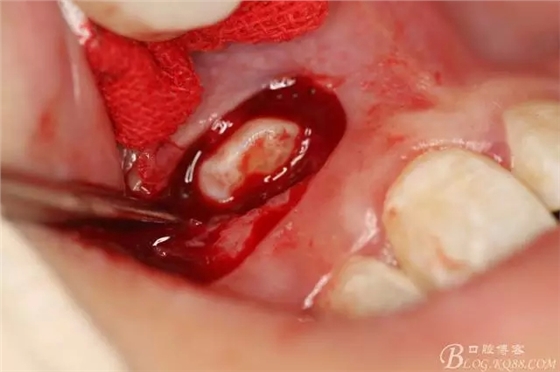

病例資料: 患者、柴xx、女、16歲。??茩z查及病歷如下圖: 患者同意我院正畸科建議,遂轉(zhuǎn)診倒外科。術(shù)前簽知情同意書。 治療過(guò)程: 圖1.術(shù)前的CBCT檢查:13阻生,疑為含牙囊腫??v剖面顯示12牙根吸收至根尖1/3。 圖2.局部麻醉下 。行唇側(cè)弧形切口,12松動(dòng)不到1°。 圖3.翻瓣、暴露骨面。 圖4.去骨、 暴露13牙冠 圖5.去骨、逐漸顯露13。 圖7.拔除13. 圖8.摘除囊壁 圖9.必須完整剝離囊壁。 圖10.摘除囊壁后形成的骨腔 圖11.超聲骨刀12根尖倒預(yù)備 圖13. 消毒棉球骨腔內(nèi)隔濕血液,紙尖干燥倒預(yù)備好的根管 圖14. 紙尖無(wú)血即可 圖15。MTA倒充填 圖16.骨腔填塞膠原蛋白海綿 圖17.拔除的13及摘除的囊壁 圖18.縫合 圖19.術(shù)后x線根尖片影像:MTA封閉根尖